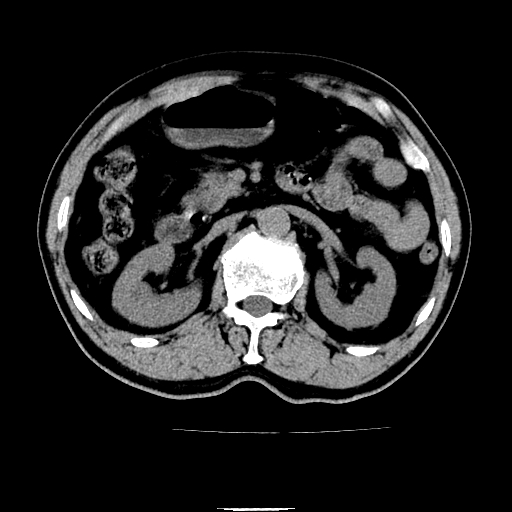

以下是引用chenqiong在2010-3-25 20:56:00的发言:[br]1、胆囊炎,胆囊息肉[br]2、肝内胆管及胆总管扩张,胆总管下端结石[br]3、十二指肠乳头旁憩室

以下是引用zxl51642在2010-3-26 10:47:00的发言:[br]胆囊炎,胆囊息肉,胆总管扩张,但未看到明显肿块,肝内胆管扩张不像恶性,炎性狭窄或阴性结石可能吧,建议mrcp,右肾小囊肿